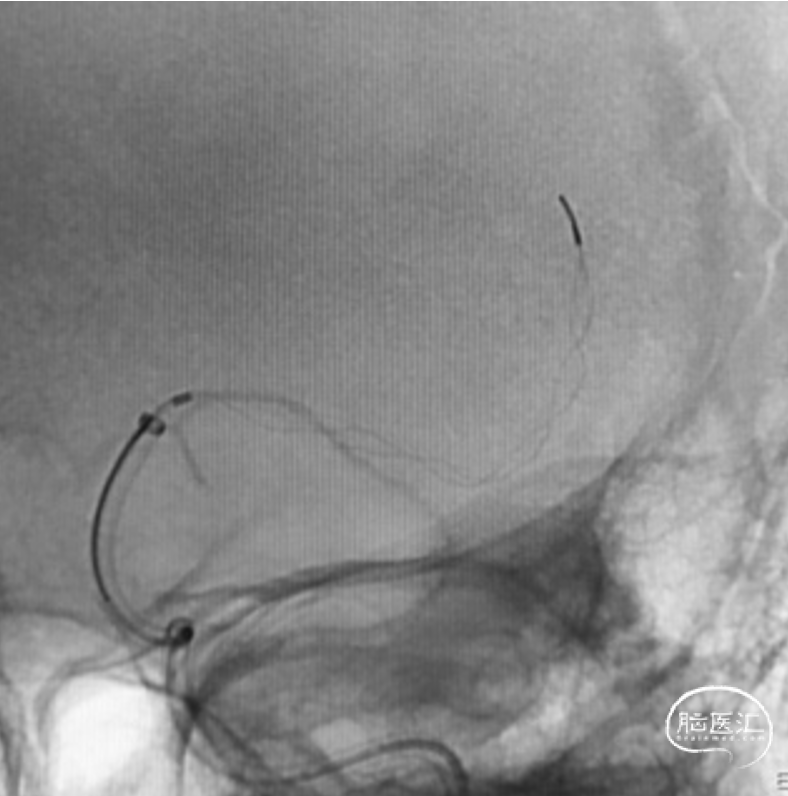

RuiFly 6F-125支撑导管到位,稳定支撑微导管到位,“冒烟”显示微导管越过血栓并在真腔。

微导管中间导管到位

输送JRecanTM 4-30mm支架到位,完全覆盖血栓,释放支架可见其全程可视并形态良好,大网孔设计,充分嵌入血栓。

应用SWIM技术,一把再通。

支架打开复流